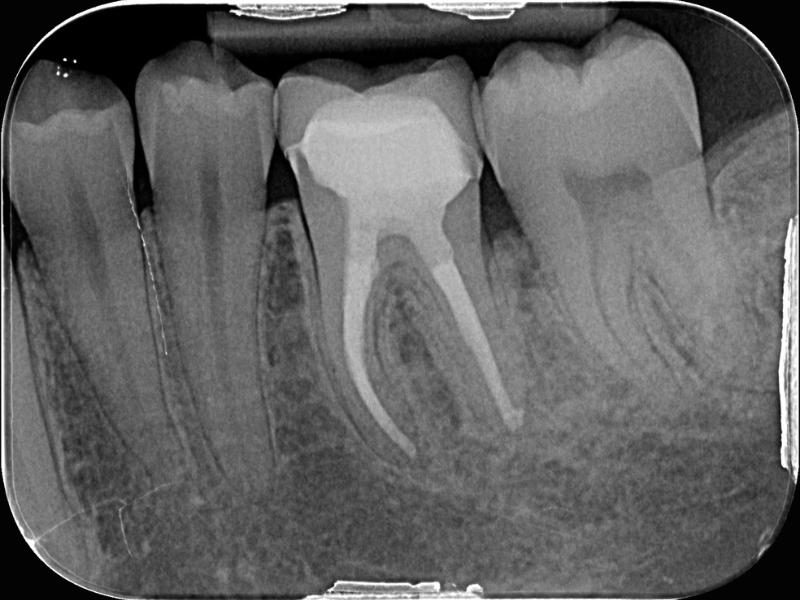

• Rimozione dei materiali da otturazione canalare: confronto tra diverse tecniche

• Recupero della lunghezza di lavoro: la chiave del successo

• Sagomatura e rifinitura apicale nei ritrattamenti: cosa cambia